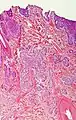

Nodular basal-cell carcinoma (also known as "classic basal-cell carcinoma") accounts for 50% of all BCC.[27] It most commonly occurs on the sun-exposed areas of the head and neck.[28]: 748 [29]: 646 Histopathology shows aggregates of basaloid cells with well-defined borders, showing a peripheral palisading of cells and one or more typical clefts.[27] Such clefts are caused by shrinkage of mucin during tissue fixation and staining.[30] Central necrosis with eosinophilic, granular features may be also present, as well as mucin. The heavy aggregates of mucin determine a cystic structure. Calcification may be also present, especially in long-standing lesions.[27] Mitotic activity is usually not so evident, but a high mitotic rate may be present in more aggressive lesions.[27] Adenoidal BCC can be classified as a variant of NBCC, characterized by basaloid cells with a reticulated configuration extending into the dermis.[27]